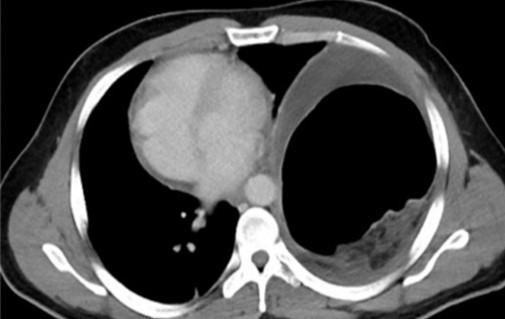

CT θώρακος-τραχήλου. Κόκκινα βέλη — Πολύ μεγάλη οπισθοστερνική βρογχοκήλη. Κίτρινα βέλη — Κλείδες (Ευγενική παραχώρηση Dr. V. Penopoulos)